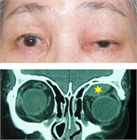

1. 縮瞳状態でも瞳孔領に上眼瞼縁がかかる眼瞼下垂は、視力不良や弱視の原因となりQOLを下げるため、眼瞼の挙上手術が推奨される(手術推奨度1)。